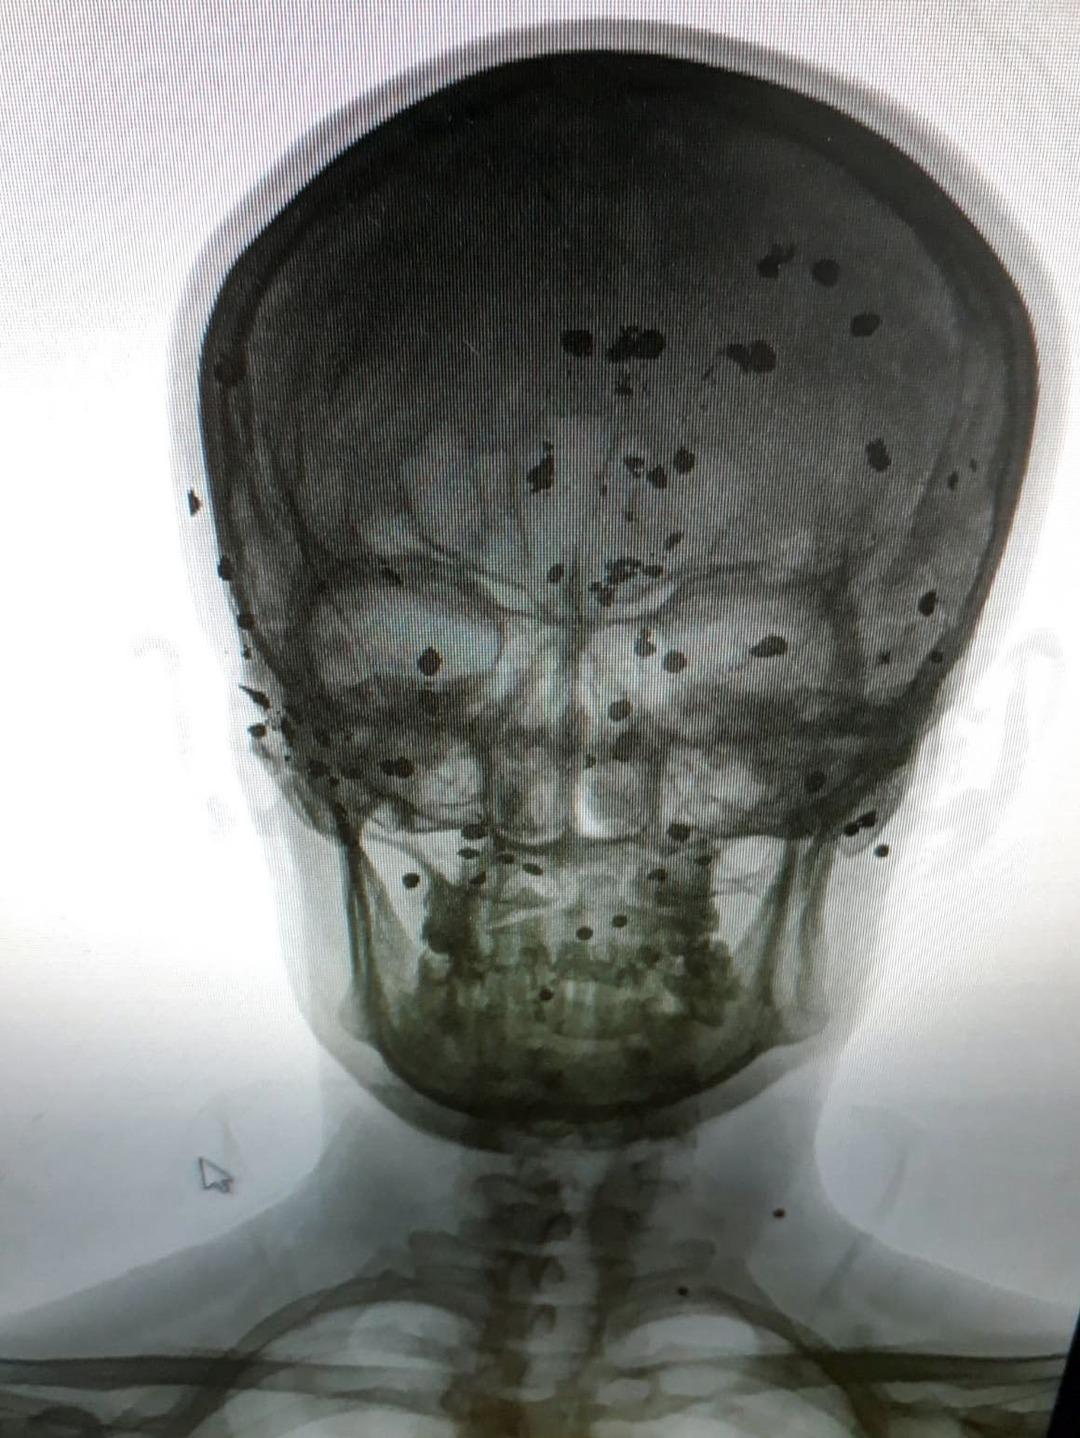

Şanlıurfa’da 43 yaşındaki terzi Abdulkadir Özeren, 20 yıl önce, gece işten çıktıktan sonra evine gittiği sırada iddiaya göre kafasına çivili zincirle kimliği belirsiz kişi veya kişilerce vurularak yaralandı.

Kafasına aldığı darbe ile yere yıkılan Özeren, kaldırıldığı hastanede tedavisinin ardından taburcu oldu. Yaklaşık bir hafta sonra kafasında şişlik oluşmasıyla tekrar hastaneye giderek röntgen çektiren Özeren, kafatasında yaklaşık 30 adet çivi ve toplu iğneye benzer metal maddelerin olduğu tespit edildi.

Bekar ve tek başına yaşayan Özeren, yaklaşık 15 kez kendi imkanlarıyla ameliyat olduğunu, tamamen iyileşmesi için ise Antalya’da olması planlanan ameliyat için maddi durumunun olmadığını ifade ederek, hayırsever işadamlarından ve devlet büyüklerinden yardım istedi. Antalya Akdeniz Üniversitesi’nde ameliyat için başvuru yaptığını aktaran Özeren, tedavi için gerekli parayı bulamazsa ameliyat olamayacağını söyledi.

Terzilik mesleğini bir ustanın yanında sürdüren fakat sağlık sorunları yüzünden sürekli işi bırakmak zorunda kaldığını dile getiren Abdulkadir Özeren, “20 yıl önce bir darbe aldım kafamdan, darbe sonucu kafam bir ceviz büyüklüğünde şişti. Daha sonra bu ceviz büyüklüğündeki şişlik patladı. İlk olarak Mehmet Akif İnan Eğitim ve Araştırma Hastanesi gittim.

Orada ilk tedavimi olduktan sonra Adana'ya sevk ettiler. Adana Balcalı Hastanesi'nde film çektiler, madde olduğunu gördük. Burada doktorlar, bana dedi ki ‘Burada seni tedavi edersek ya kör olursun ya da felç kalırsın’ daha sonra tedavi olmadım. Öyle kaldım. Maddi imkanlarım olmadığı için başka yere de gidemedim. Daha sonra askerlik çağım geldi, askere gittim. Askerlik yaparken fenalaştım tedavi için Isparta'ya gönderildim. Isparta'da 4 kez ameliyat oldum.